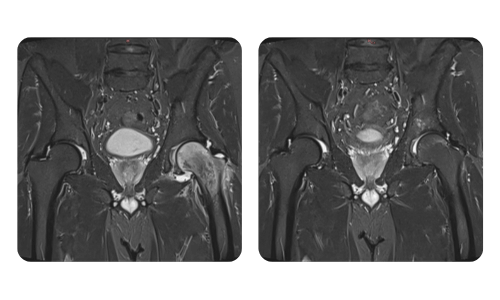

Betegeink előrehaladása, amelyet a hiperbár terápia előtt és után mértünk, tükrözi a kezelés hatékonyságát és pozitív hatását. Fedezze fel a Hyperbarium Oradea hiperbár terápiájának dokumentált eredményeit, amelyek klinikai értékeléseken és objektív adatokon alapulnak, és jelentős javulásokat mutatnak különböző állapotokban.